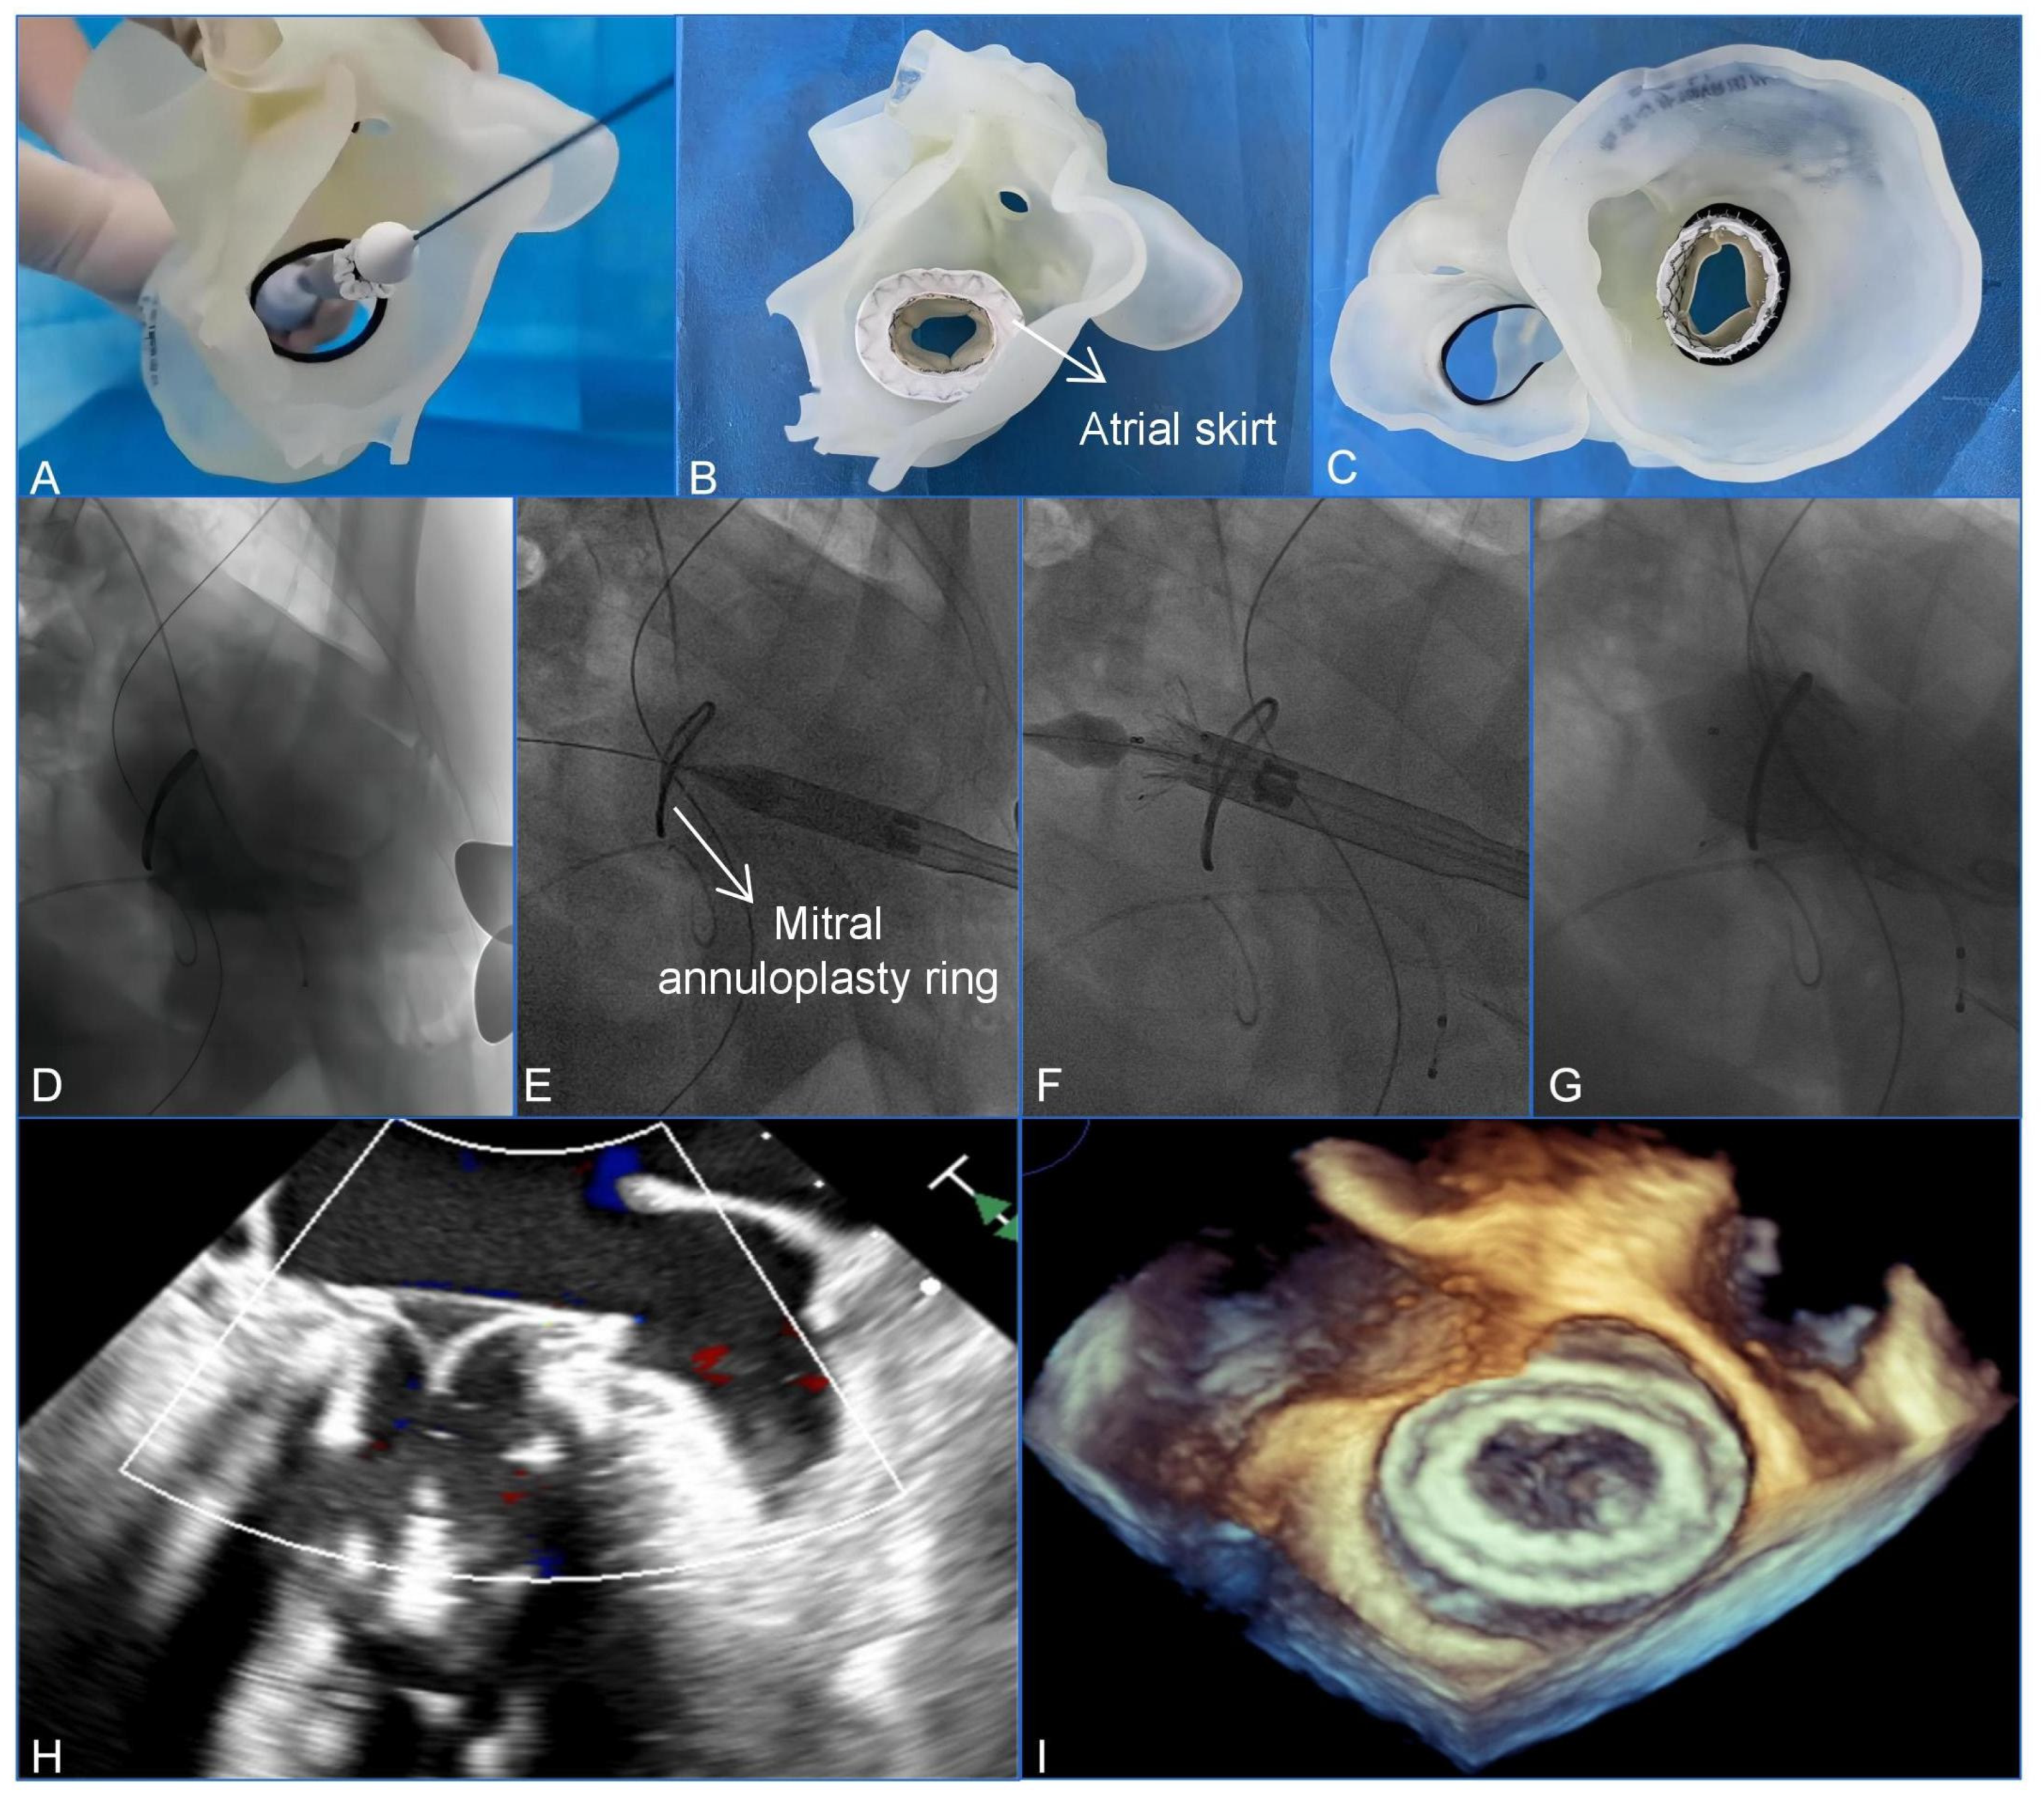

The procedure was conducted with the patient under general anesthesia and mechanical ventilation. Intraoperative guidance was provided using fluoroscopic images and TEE. A 4 cm left anterior mini-thoracotomy incision was made to access the puncture point at the apex of the left ventricle. Puncture and cannulation were carried out using 6F sheaths on both the right femoral artery and vein. Subsequently, a temporary pacemaker electrode was carefully inserted into the right ventricle through the vein sheath. At the same time, a 6F pigtail catheter was advanced from the right femoral artery to the left ventricle. We successfully obtained standard apical access and secured the entry site using a hexagonal suture. To optimize visibility of both the left ventricle and atrium, we made adjustments to achieve a cranial right-anterior-oblique angulation. Ventriculograms were performed to evaluate the MR and to assess the shape of the left ventricle and the mitral annuloplasty ring. Based on the preoperative assessment and simulation conducted using the patient-specific3D-printed model (Figure 2A–C), the assembly of a 33 mm Mi-thos bioprosthesis onto the delivery system was performed in vitro. To begin the procedure, an apical puncture was made, and a 6 Fr sheath was inserted. A 6F pigtail catheter, along with a J-tipped 0.035-inch guide wire, was then guided across the mitral surgical ring and into the left atrium. Following this, a 260 cm Lunderquist super stiff wire (Cook Medical Inc., Bloomington, IN, USA) was then used for exchange. The delivery system was inserted over the Lunderquist guide wire and advanced in a retrograde manner across the mitral annuloplasty ring via the transapical approach, ultimately reaching the left atrium. By retracting the outer sheath of the delivery system, the atrial skirt, which was specifically designed to fit the D-shaped mitral annulus, was released. It completely covered the mitral annulus and the annuloplasty ring, guided by TEE and fluoroscopy, while the ventricular portion of the device remained partially confined to the sheath. After confirming the position and alignment of the Mi-thos valve, the entire system was retracted and properly seated on the mitral annuloplasty ring. Subsequently, under rapid pacing at a rate of 140 per minute, the ventricular portion of the bioprosthesis was released and securely anchored to the native MV using secure barbs.

Immediately ventriculograms confirmed the excellent position and shape of the Mi-thos valve, with no evidence of transvalvular regurgitation, paravalvular leak (PVL), or left ventricular outflow tract obstruction (LVOTO) (the area of the neo-left ventricular outflow tract was 374.6 cm2). The valve’s position and function were further assessed using TEE, which indicated a mean pressure gradient of 3 mmHg (Figure 2D–I, Videos S1 and S2). Subsequently, the delivery system was carefully removed through the apex incision, and hemostasis was achieved using the apical strings that were previously placed. After closing the incision, the patient was successfully weaned off the ventilator and transferred to the cardiac intensive care unit. The postoperative recovery was smooth, and the patient was discharged in good clinical condition 5 days after the operation. At the time of discharge, the transthoracic echocardiogram examination confirmed the excellent position and function of the valve. Additionally, there was no evidence of any significant transvalvular or paravalvular regurgitation, as well as no LVOTO, and the maximum and mean gradients were measured at 6 mmHg and 2 mmHg, respectively. The patient’s symptoms had improved (NYHA functional class II).

Figure 2. Preoperative assessment and simulation of and main procedural steps for transcatheter mitral valve-in-ring replacement. (A) Adjustment of coaxiality and of the release position. (B,C) The stent was fully unfolded and observed in the left atrial and the ventricular views. (DG) The main steps of the procedure. (D) Fluoroscopy revealed severe mitral regurgitation. (E) The delivery system was advanced via the transapical approach. (F) Initial release of the stent. (GI) After the stent was fully released, fluoroscopy, and transesophageal echocardiography revealed that the bioprosthesis was in a stable position and functioning well without paravalvular leak.